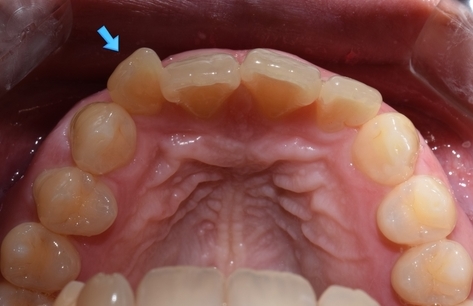

단, 이 케이스에서 화살표의 치아는 너무 많이 튀어 나와있었으므로

이 치아만 삭제를 진행하여 라미네이트가 아닌 크라운으로 진행하였습니다.

라미네이트로 두께를 0.1(거의 차이나지 않게)부터 무한대까지 늘릴 수는 있지만

무언가를 붙이면서 있던 치아의 두께를 줄이는 것은 삭제가 없이는 불가능 하죠.

따라서 위의 화살표 치아는 많이 깎아야 하기 때문에 라미네이트가 아닌 크라운을 씌우는 방식으로 진행하였구요